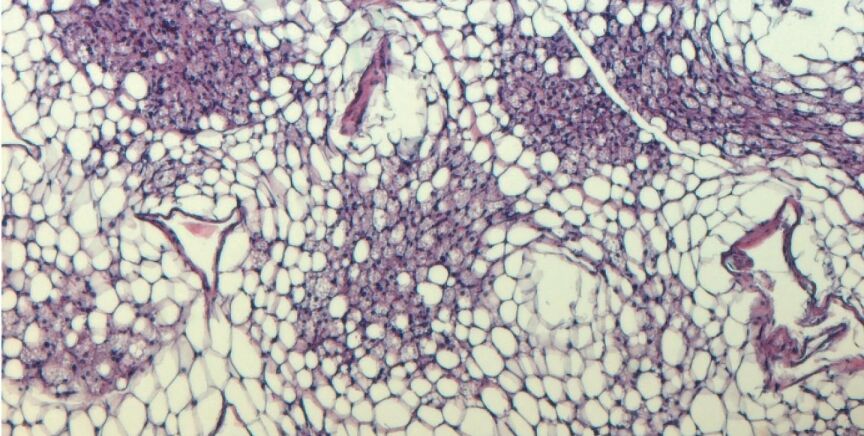

Junto con un grupo de colegas, el equipo de la Universidad de Bonn ha identificado ahora una molécula clave llamada inosina que es capaz de quemar grasa. "Se sabe que las células moribundas liberan una mezcla de moléculas mensajeras que influyen en la función de sus vecinas. Queríamos saber si este mecanismo también existe en la grasa parda", detalla Birte Niemann, otro de los autores de la investigación.

Por ello, los investigadores estudiaron las células de grasa parda sometidas a un estrés severo, de modo que las células prácticamente morían. "Descubrimos que segregan la purina inosina en grandes cantidades", dice Niemann.

Sin embargo, lo más interesante fue cómo las células de grasa parda intactas respondieron a la llamada de auxilio molecular: Se activaron por la inosina (o simplemente por las células moribundas de su entorno). Así, la inosina avivó el fuego en su interior. Las células de grasa blanca también se convirtieron en sus hermanas marrones. Los ratones alimentados con una dieta alta en energía y tratados al mismo tiempo con inosina se mantuvieron más delgados en comparación con los animales de control y quedaron protegidos de la diabetes.